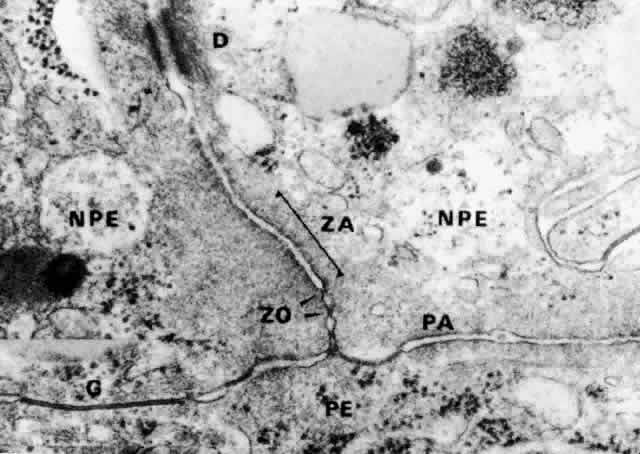

The zonula occludens is the primary component of the blood-aqueous barrier “tight

junction.” It appears as a focal area at which

the bilayered plasmalemmal membranes of each cell surface are tightly

joined (Fig. 20). Zonular adherens junctions occur adjacent to occludens junctions on

the basal side. They show a 12- to 15-nm space between the adjoining cells, with

filamentous matrix material clinging to the cell membranes

on either side. By the freeze-fracture technique, the zonula occludens

consists of branching anastomosing strands on the cytoplasmic side of

the plasmalemmal membrane (P-face) and matching grooves on the external

side (E-face), giving a quilted effect (Fig. 21). The variation in number of strands seen from area to area in the ciliary

zonula occludens region23 is consistent with physiologic evidence that the NPE is leaky to ions

and small molecules, rather than being an absolute barrier like that between

the endothelial cells of the retinal vessels. Ohnishi and Kuwabara24 found the tight junctions of the anterior pars plicata had the fewest

strands, explaining why this region is so sensitive to leakage after paracentesis

in several species.  Fig. 20. Apical junction of two nonpigmented epithelial cells (NPE) showing focal

zonula occludens (ZO) junctions (arrows), an adjacent zonula adherens (ZA), and

desmosome (D), puncta adherentes (PA), and gap (G) junctions. PE, pigmented

epithelium. (X 58,700) Fig. 20. Apical junction of two nonpigmented epithelial cells (NPE) showing focal

zonula occludens (ZO) junctions (arrows), an adjacent zonula adherens (ZA), and

desmosome (D), puncta adherentes (PA), and gap (G) junctions. PE, pigmented

epithelium. (X 58,700)